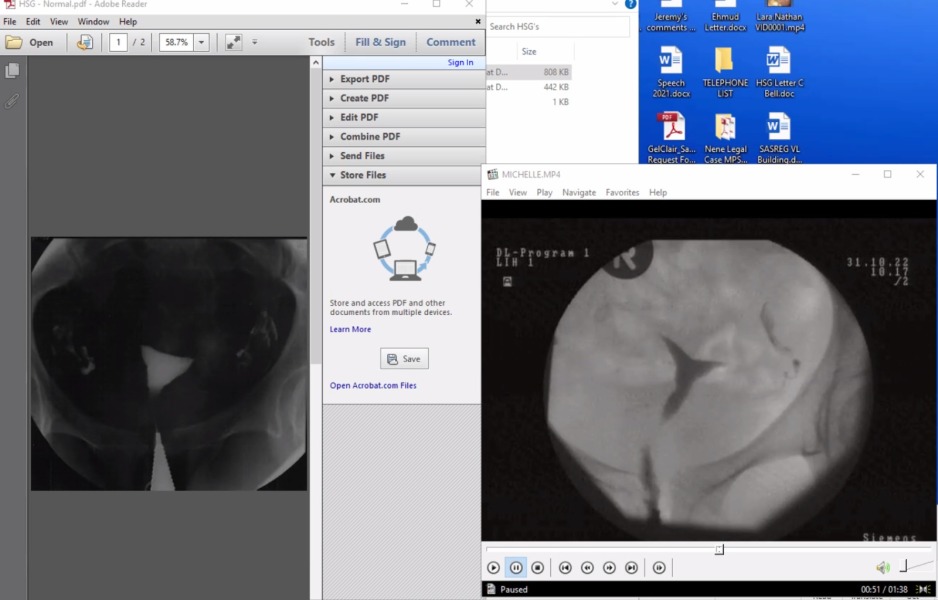

Hi, I've had 2 missed miscarriages and 2 chemical pregnancies in the past 3 years. I've been to an NHS miscarriage clinic as well as to a private clinic specialising in recurrent miscarriage (CRP clinic; which I've been going to for the past year and a half for treatment). We were about to give up, but while on a trip to South Africa, decided to see another specialist here. They suggested an HSG x-ray, which has shown that I have a misshapen uterus and they believe this has caused my miscarriages. I wasn't ever offered this test, by any of the doctors I've seen.

PLEASE, if you're struggling with this issue, ask your doctor for this procedure. It will help them to see if there is anything structurally wrong, whether there is scarring and will flush your fallopian tubes (if needed). I wish I'd known to ask, so I'm hoping to spread the word. It might not give you the answers you're looking for, but I feel like, if you've suffered from multiple miscarriages, you should at least be offered this as part of the investigations.

I've added the image from my HSG - my 'weird' uterus in on the right and a normal one is one the left.

Anyway, i just wanted to spread awareness. If you have any questions, I'll do my best to answer them, but if you think it might help to give you answers, speak to your doctor about getting it scheduled